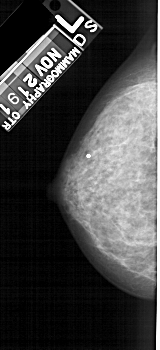

A_1472_1.RIGHT_MLO

LEFT_CC LINES 4891 PIXELS_PER_LINE 2236 BITS_PER_PIXEL 12 RESOLUTION 43.5 NON_OVERLAY

LEFT_MLO LINES 5371 PIXELS_PER_LINE 2506 BITS_PER_PIXEL 12 RESOLUTION 43.5 NON_OVERLAY